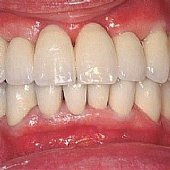

• Die fertige festsitzende Versorgung mit Keramikbrücke.

• Die Lachinie der fertigen festsitzenden Versorgung mit Keramikbrücke.